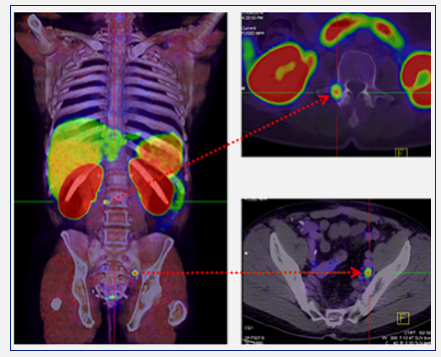

The PET-CT images

Positron emission tomography–computed tomography (PET-CT) is a global best practice diagnostic imaging tool that captures three-dimensional images of the body's biological functions. By utilising a small amount of a radiotracer (a radioactive substance that is used in medical imaging*), PET-CT scans can detect areas of abnormal metabolism or function in the body, including fast-growing cancers and infections.

PET-CT scans help doctors pinpoint the location of tumours or cancerous lesions, assess the extent of disease, determine whether lesions are benign or malignant, and identify any potential spread.